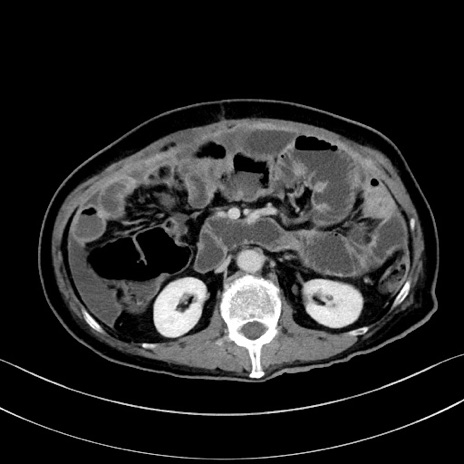

症例28(横断像)

【症例】60歳代男性

【主訴】嘔吐

【現病歴】胃癌にて胃全摘後。食思不振が悪化し、夜中に嘔吐することがある。

【既往歴】胃癌、胃全摘、脾摘、胆摘後

【データ】WBC 5900、CRP 10.56